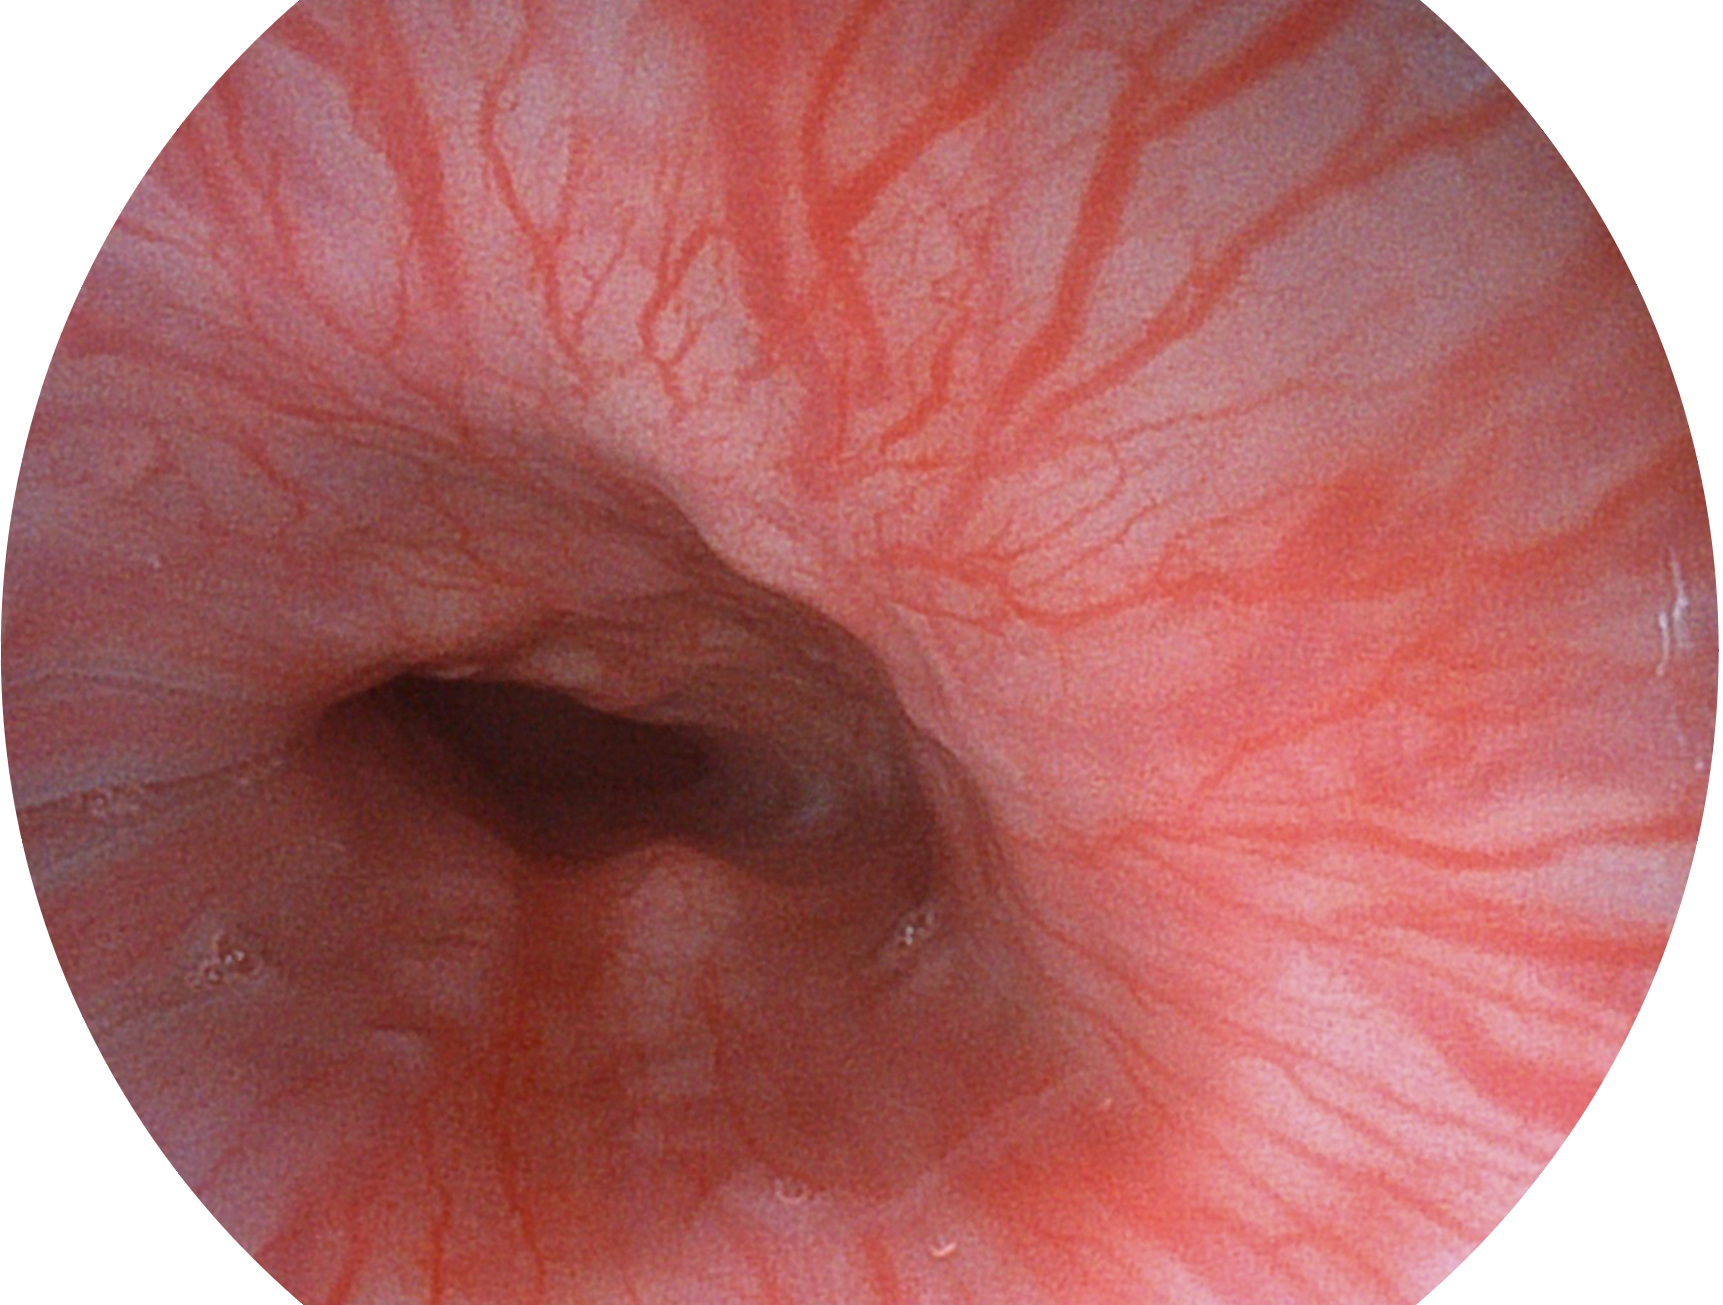

開立新開發(fā)的內(nèi)鏡染色技術(shù),主要是基于多波長(zhǎng)LED 光源的開發(fā),VLS-55Q 四波長(zhǎng)LED 光源是由四個(gè)不同顏色的LED光按照相應(yīng)照明模式所規(guī)定的特定發(fā)光比例進(jìn)行合束后形成,合束后形成的照明光的光譜由紅光、綠光、藍(lán)光及藍(lán)紫光這四個(gè)不同的波段范圍構(gòu)成。具有更高光譜自由度,通過(guò)光譜比例的控制,實(shí)現(xiàn)了聚譜成像技術(shù),英文全稱為“Spectral Focused Imaging, SFI”,縮寫為“SFI”和光電復(fù)合染色成像技術(shù),英文全稱為“Versatile Intelligent Staining Technology, VIST”,縮寫為“VIST”。